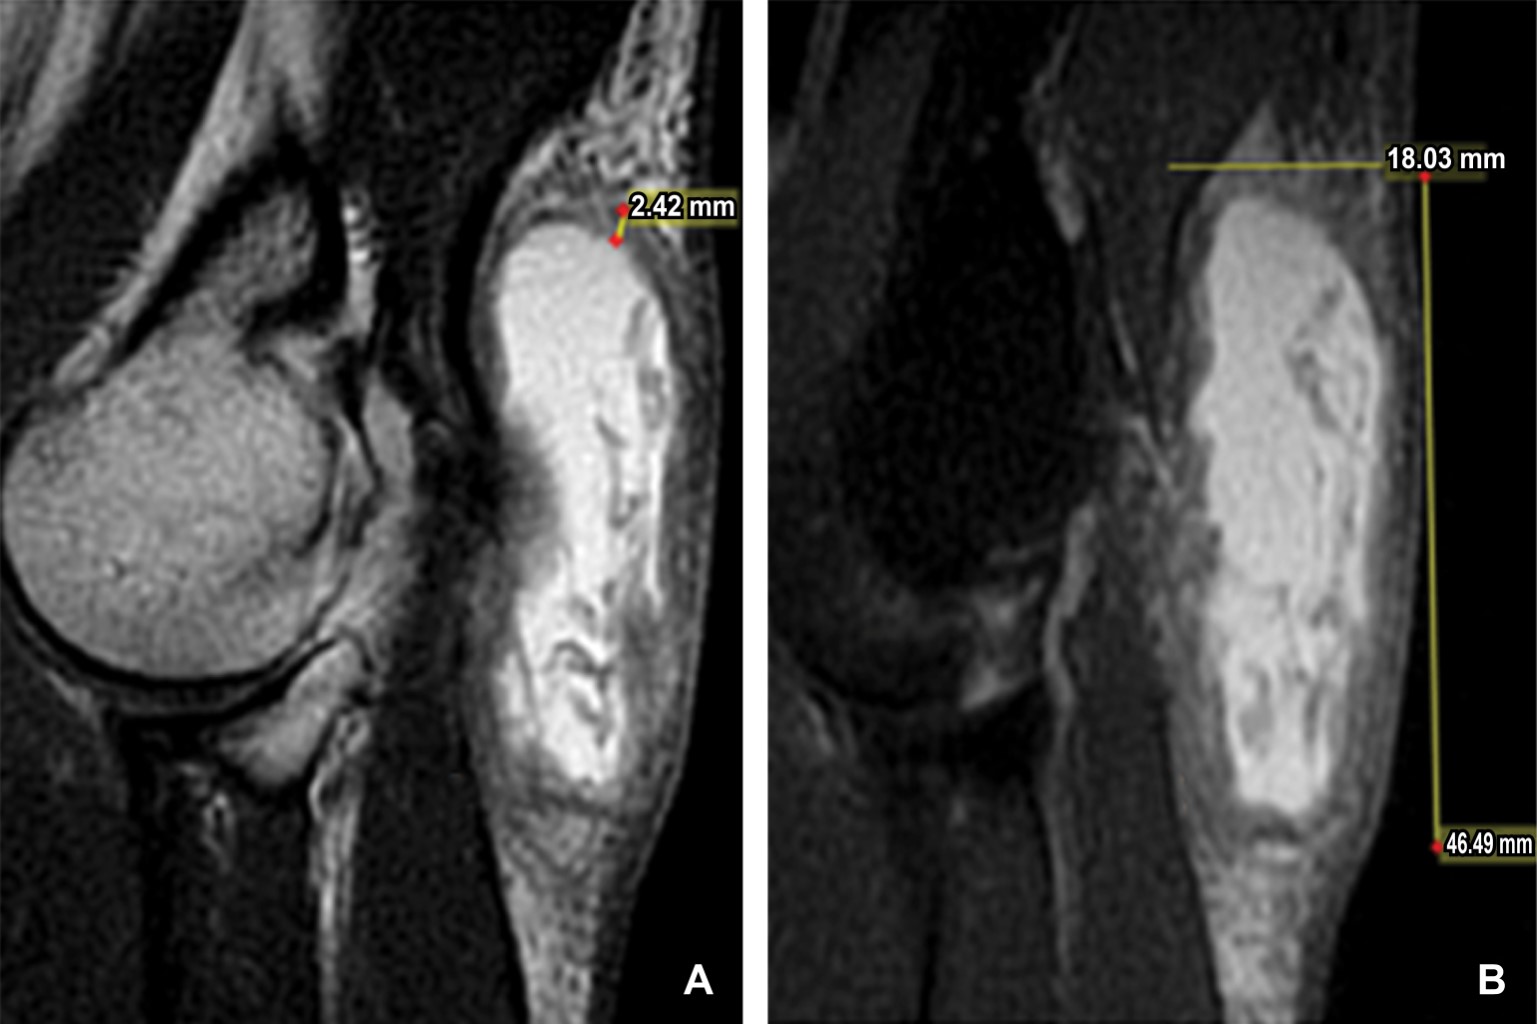

Masculino de 40 años de edad que refiere aparición de zona de enrojecimiento y pequeño abultamiento a nivel del codo izquierdo de tres semanas de evolución, inicialmente adjudicada a piquete de insecto. Acude a médico particular que le administra tratamiento antibiótico sin mejoría, por lo que acude a una segunda evaluación médica donde a la exploración física se evidencia un notable aumento de volumen en región olecraneana, de consistencia blanda con eritema, razón por la que su médico decide investigar a fondo y solicita estudios de laboratorio, los cuales revelaron una elevación de los niveles séricos de ácido úrico y se diagnosticó con gota, por tal motivo se solicita resonancia magnética de codo izquierdo. En el estudio de resonancia magnética simple se identifica una imagen sacular a nivel del olecranon, bien delimitada, heterogénea en su interior, de comportamiento isointenso heterogéneo en el T1, hiperintenso heterogéneo en el T2 e hiperintenso heterogéneo en el T2 con saturación grasa. Dicha imagen midió 39.8 × 14.8 mm en el plano axial, 18 × 46.5 mm en el plano sagital y 40.21 × 46.07 mm en el plano coronal (Figuras 1, 2 y 3), con una pared que midió 2.42 mm de grosor (Figura 2); localizada a nivel de las bursas del olécranon en específico a nivel de la bursa olecraneana superficial.

Figura 2